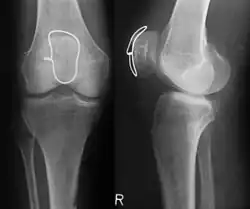

-

Klassische Zuggurtung einer Patellafraktur -

Erweiterte Zuggurtung einer Patellafraktur (mit K-Drähten) -

Eine Bimalleolarfraktur im seitlichen Röntgenbild … -

… und von vorne … -

… mit Zuggurtung am Innenknöchel und Platte am Außenknöchel versorgt